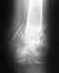

У меня закрытый перелом наружной ладышки, повреждение синдесмоза, подвывих стопы кнаружи.